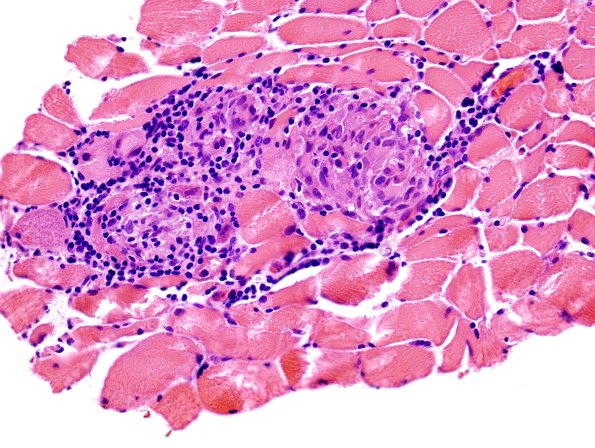

1B2 Sarcoid, no bugs (Case 1) muscle H&E 1

Sarcoid, in distinction to leprosy, do involve skeletal muscle (H&E)